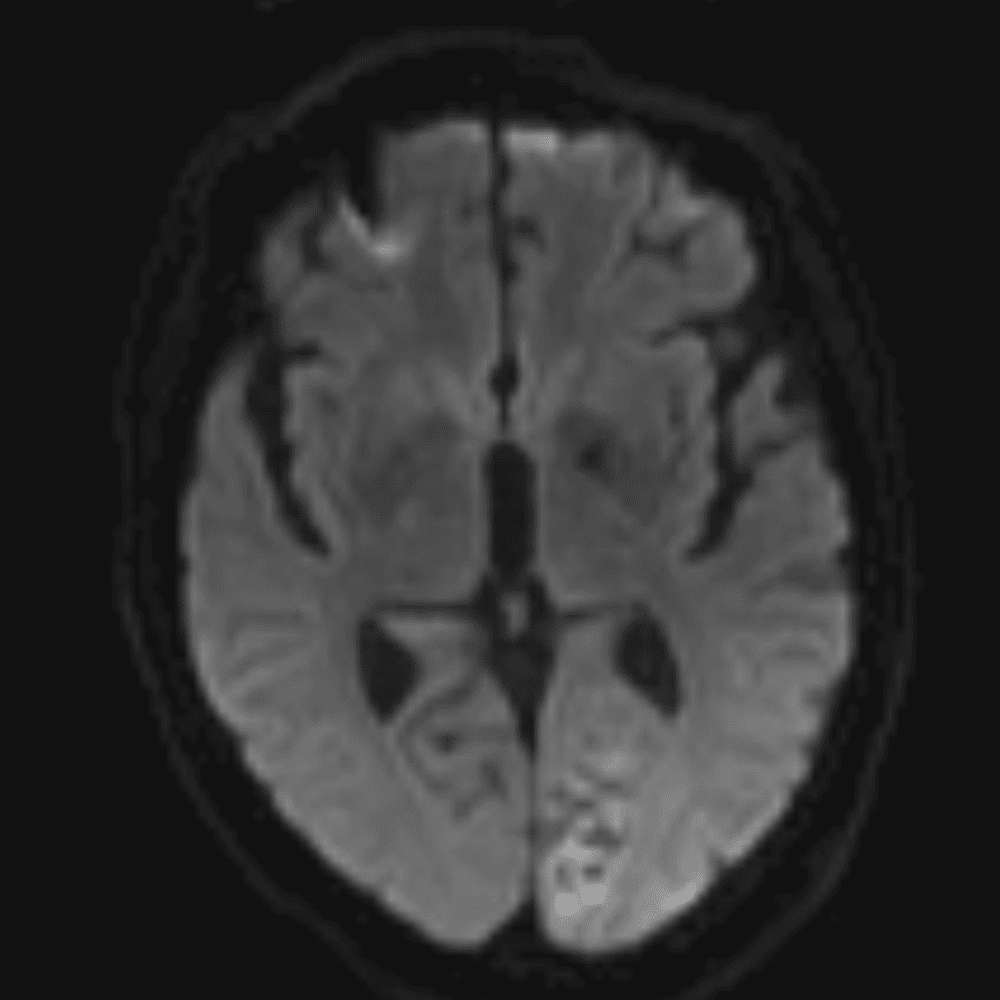

๋‹น์ง ์‹œ ํ”ํžˆ ๋ณผ ์ˆ˜ ์žˆ๋Š” ์‚ฌ๋ก€์˜ ์ „ํ˜•์ ์ธ ์˜ˆ๋ฅผ ํฌํ•จํ•ฉ๋‹ˆ๋‹ค.

39 ์‚ฌ๋ก€

์—ฐ์Šต

๋ฏธ๋ฌ˜ํ•˜๊ฑฐ๋‚˜ ์–ด๋ ค์šด ์‚ฌ๋ก€์™€ ์ผ๋ถ€ ์ •์ƒ ์‚ฌ๋ก€๋ฅผ ํฌํ•จํ•˜์—ฌ ๋‹น์ง์„ ์‹œ๋ฎฌ๋ ˆ์ด์…˜ํ•ฉ๋‹ˆ๋‹ค.

50 ์‚ฌ๋ก€